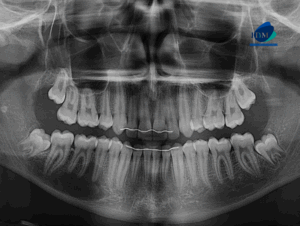

Caso 346 – IDM – MESIODENT EN POSICIÓN INVERTIDA – IDM